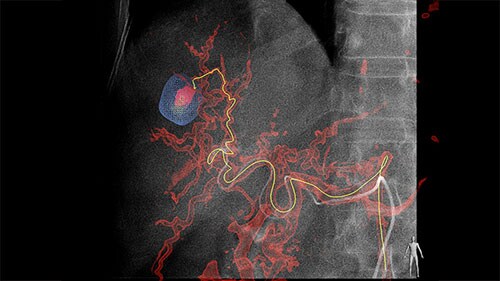

Step 2 – Reach

Based on these images, EmboGuide’s automatic feeder detection can detect significantly more feeding vessels than the current treatment standard of DSA.² ⁴

Live Image Guidance then supports selective or super-selective approaches to the embolization target.